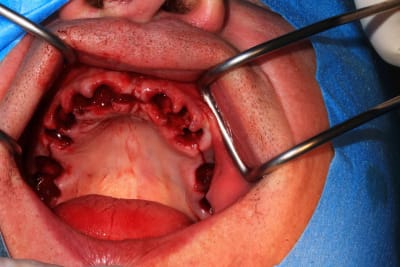

Le cas N°2 en images reelles :)

Guide métal avec support clavette, os assez fin : il est prévu un sticky bone complet : donc : lambeau avant extraction, positionnement du guide base et forage des clavettes, positionnement du guide implant, pose des piliers MU, controle des axes prothétique avec le guide pilier, collage des piliers prov sur le bridge a armature métal, occlusion nickel, sticky bone et PRF, sutures suspendues.

Voilà les photos du cas , avec un peu de retard.